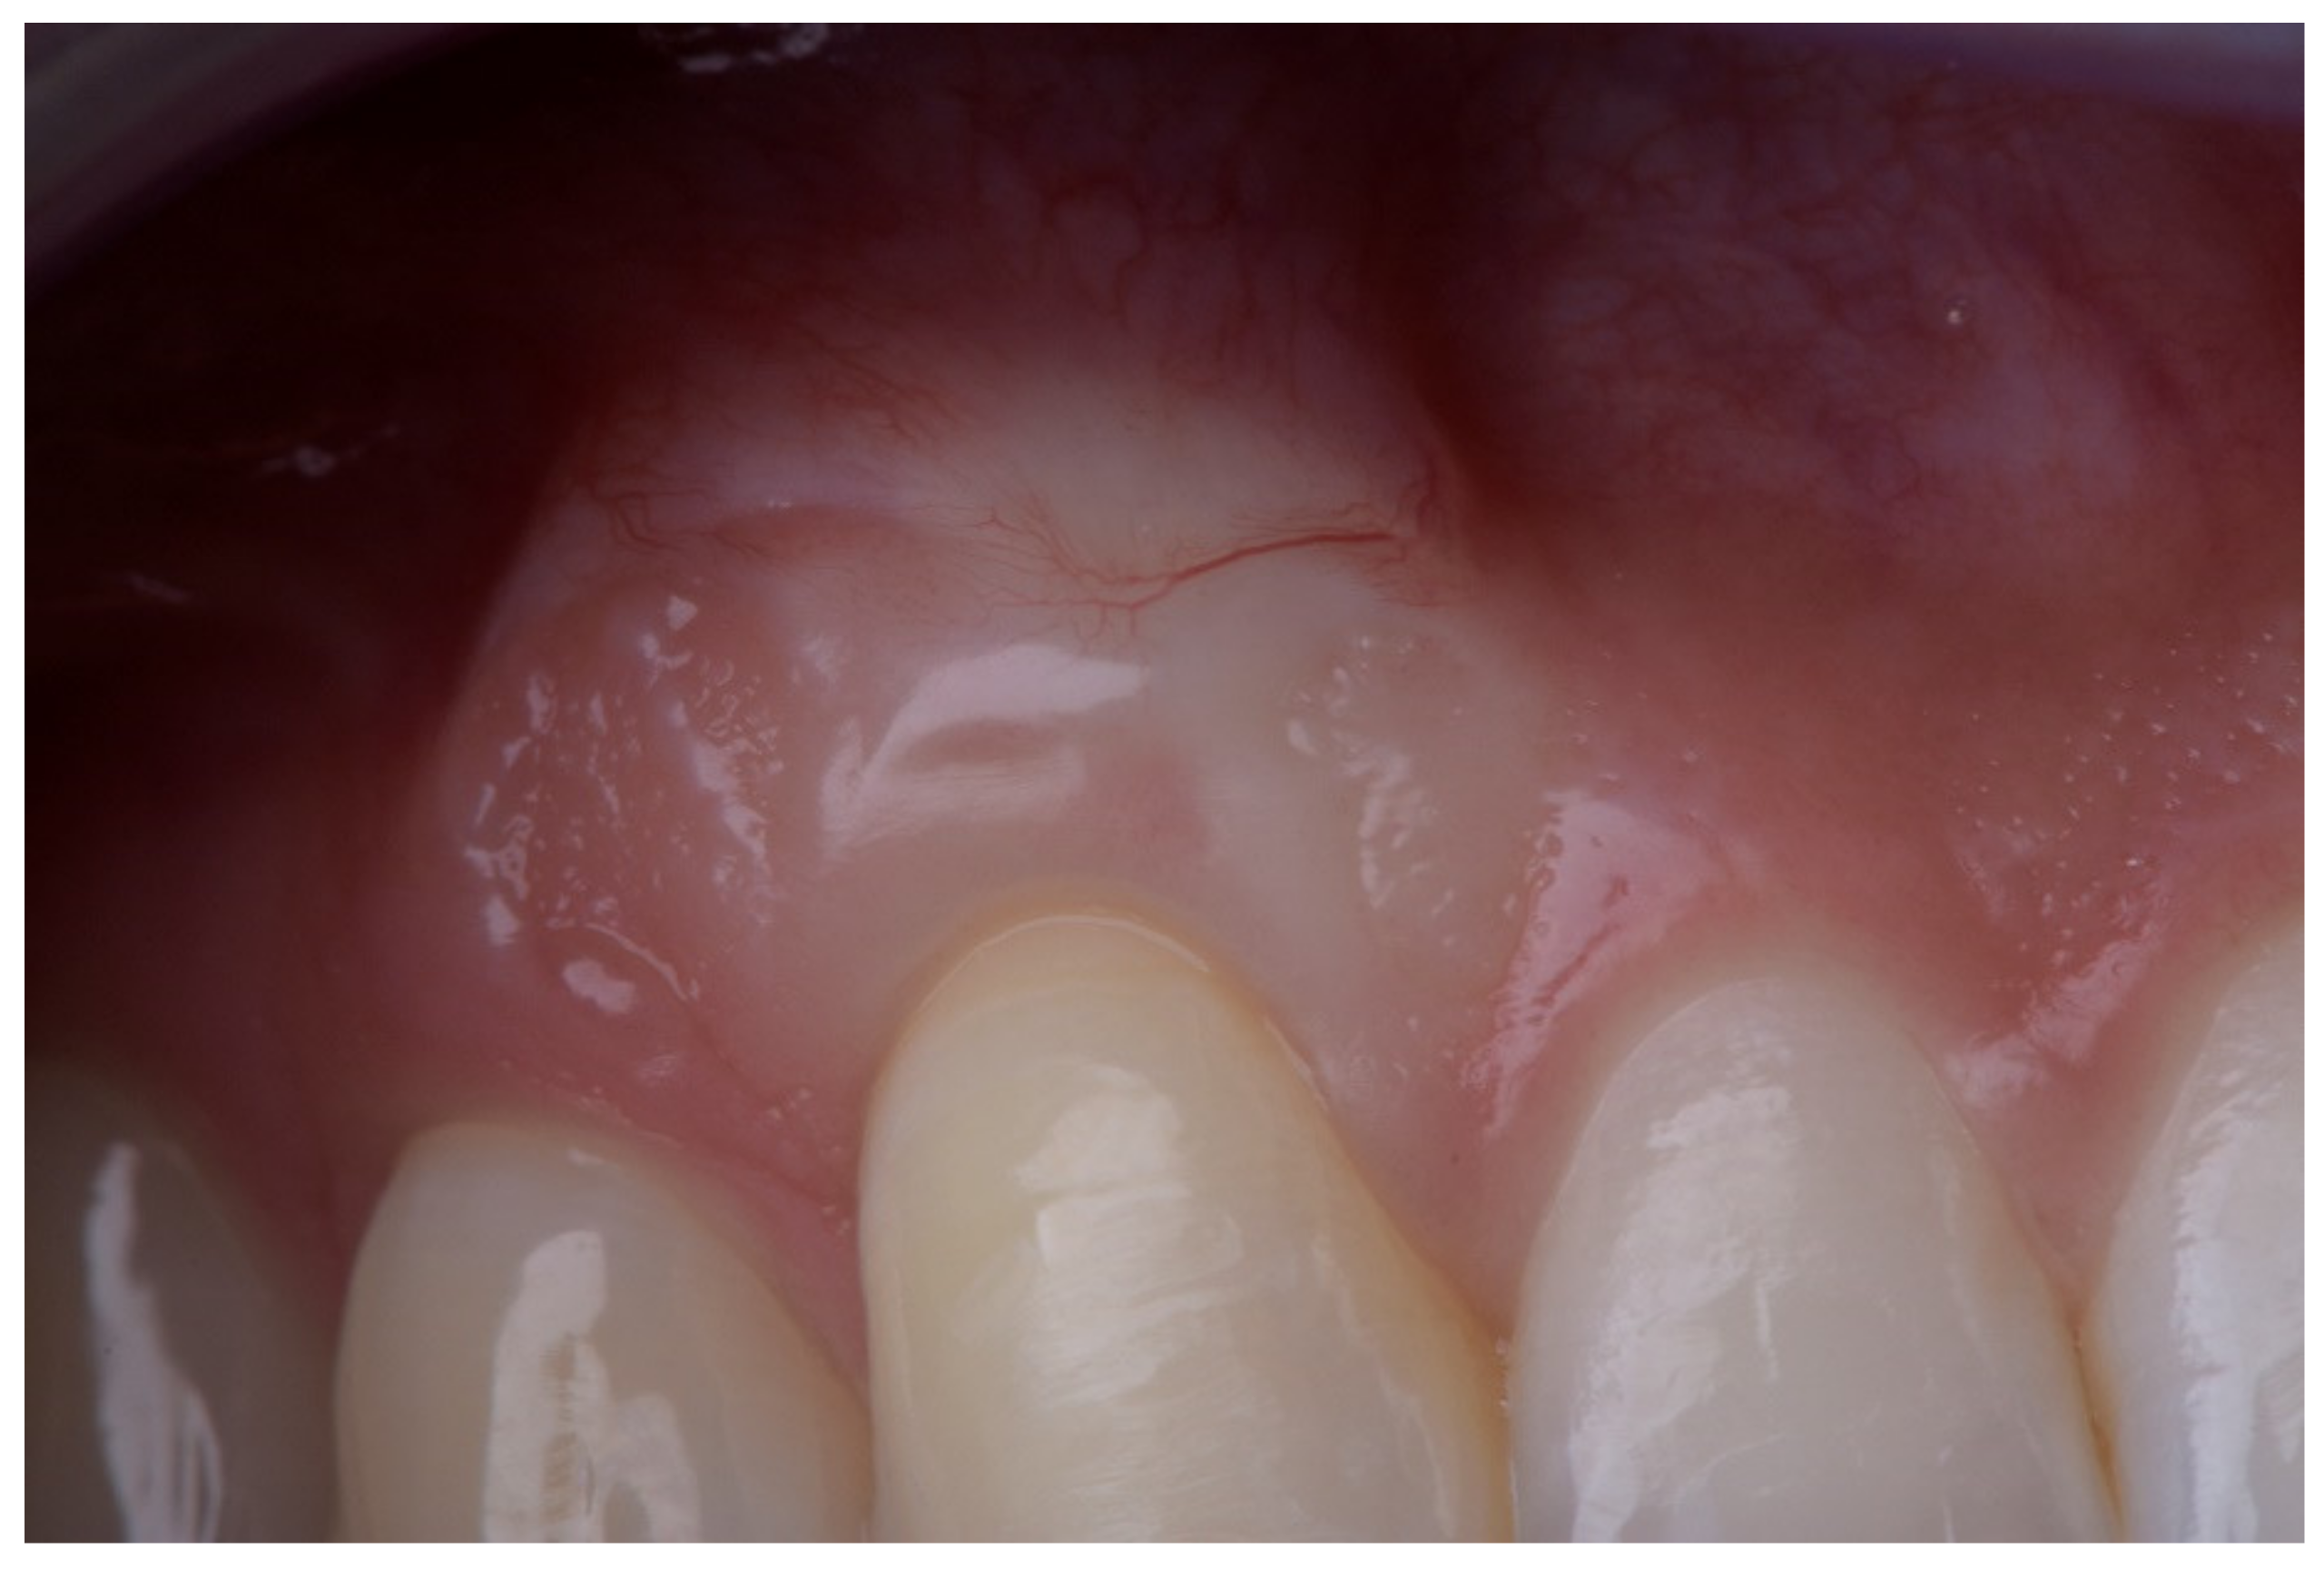

- Superficial revascularization: proliferation of multiple blood vessels modifying the superficial aesthetics of the graft. (Figure 5).